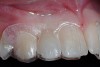

The 3-month postoperative views can be seen in Figure 18 through Figure 20. Note the excellent soft tissue emergence profiles obtained from the properly contoured provisional restorations. After removal of the provisional restorations, further inspection of the contoured emergence profile obtained has been accomplished (Figure 21 and Figure 22). Before impression techniques, transfer copings were seated over the abutment portion of the one-piece implant (Figure 23). A full-arch impression was then taken using medium-body impression material (Take 1 Advanced, Kerr Corporation, Orange, CA) and a regular-body wash material (Take 1 Advanced) to pick up the detail of the emergence profile and impression coping (Figure 24 through Figure 26). After allowing the impression material to set, the impression is then removed from the mouth and inspected (Figure 27). The Take 1 Advanced Medium body has a more rigid set than most other medium materials, so when the coping is placed back in the impression, the possibility of movement during casting is reduced. Please note how the emergence profile obtained has been registered in the impression, and can easily be transferred to the laboratory technician. Laboratory analogues are then placed into the impression coping and forwarded to the laboratory technician for pouring of the casts and final fabrication of the esthetic implant restorations (Figure 28).